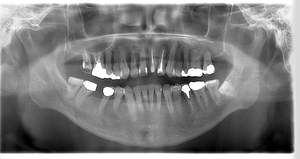

レントゲン写真

- Befor

- After

| 年齢 | 50代・男性 |

|---|---|

| 主訴 | 左上7番 左下5番7番 |

| 治療内容 | ・インプラント埋入 ※1:GBR(骨造成)・・・骨再生誘導法。骨の高さや厚みを人工骨や人工膜などを使用し再生する方法 |

| 治療費 | 合計:1,809,500円(税込) ■内訳 ・左上7番 ・左下5番7番 |

| 治療期間 | 左上7番約1年 左下5番7番約10ヵ月 |

| 治療方針 | 左上7番は昔他院で被せものをしており、被せものの中が歯ぐきの中まで虫歯になっていたため抜歯せざるを得ない状態だった。抜歯と同時に骨造成を行い、骨が出来るまで4ヵ月待ってからインプラントを埋入した。 ※2ポンティック・・・歯のない部分を補うダミーの歯。 |

| 担当者所見 | 元々金属の被せものが多く入っていたため、2次カリエス※3が多かった。今回は金属ではなく、ジルコニアを使用し、2次カリエスにならないよう、患者様にはブラッシング指導とメンテナンスの重要性をお伝えした。 ※3二次カリエス・・・詰め物や被せものを入れた歯が虫歯になること。 |